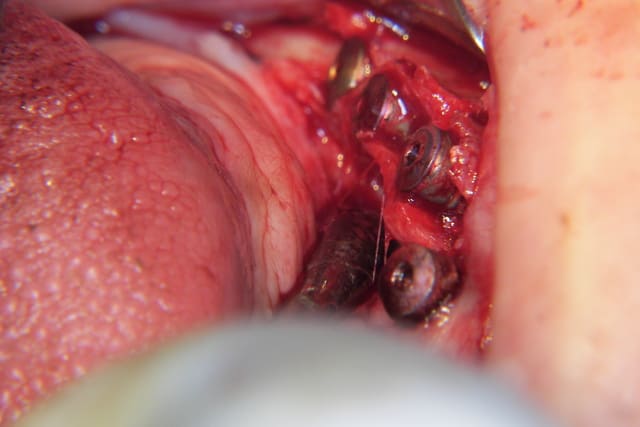

J'ai essayé pour une implantation mandibulaire (45-46): malgré les décharges osseuses le splitting était très difficile car corticale épaisse, du coup j'ai sectionné l'os en apical pour m'en sortir, sans aller jusqu'à la fracture osseuse cependant (quoique pourquoi pas?).

Effectivement Growler, la crête atrophique à la mandibule est souvent dense (type 1 à 2); il est difficile réaliser une mobilisation du volet vestibulaire avec les seuls osteotomes. Pour augmenter l'élasticité du volet osseux vestibulaire, une incision longitudinale basale de décharge es très souvent nécessaire en plus des incisions verticales et crestale. Cette incision longitudinale augmente la résilience et soulage la mobilisation du volet osseux vestibulaire. Ce dernier peut très facilement après mobilisation être transvissé et fixé par des vis d'osteosynthèses classiques.

Il est à mon avis préférable d'obtenir un trait de fracture propre et maitrisé plutôt qu'un volet vestibulaire fragilisé, traumatisé et abimé.

Splitting mandibulaire nnrckm - Eugenol